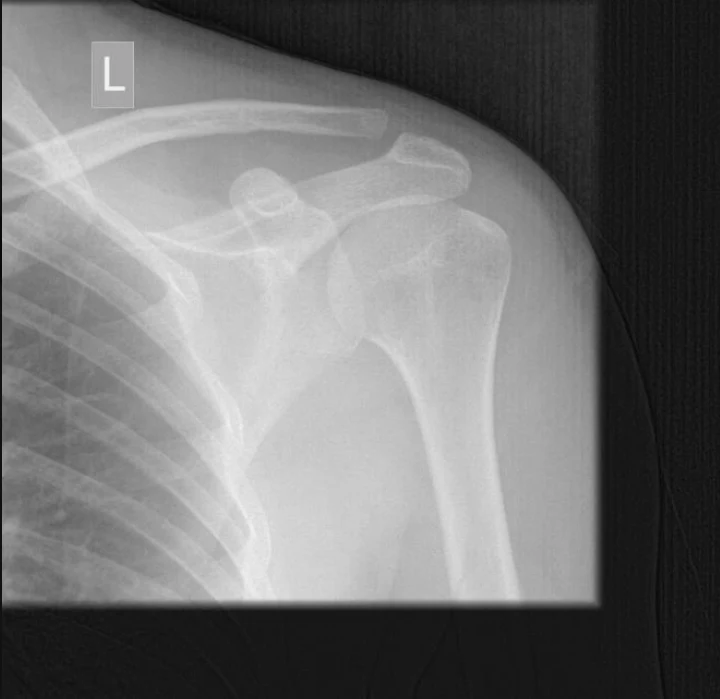

Jak widzicie, życie dziennikarza wcale nie jest takie miłe i bezpieczne. Nam też zdarzają się wypadki w czasie pracy. Redakcyjny kolega przypłacił jeden z wywiadów... złamanym obojczykiem!